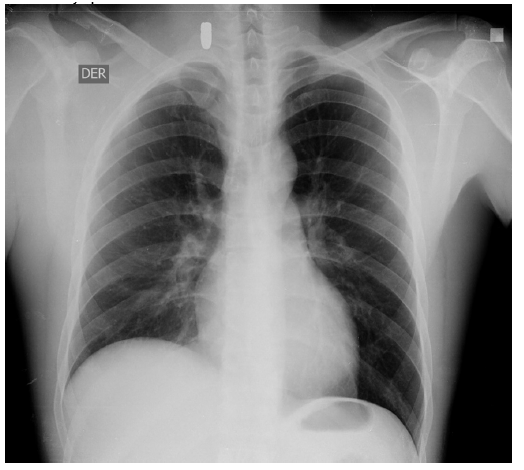

A 31-year-old man with no previous medical history was taken to the emergency department after suffering multiple injuries from a firearm, a chest wound and two in the right upper extremity, at a distance of approximately 8 meters, the gun caliber is unknown. The patient was alert, oriented with Glasgow 15/15 coma scale, normal vital signs, central and peripheral pulses, strong and symmetric, hemodynamically stable and negative shock index. The physical examination showed wounds with an entrance and exit hole in the proximal third of the right upper limb, another entrance and exit hole at the level of the hand of the same extremity. An entrance orifice was identified in the right deltoid region, without exit orifice. No wound had hard or soft signs of vascular injury. The initial chest radiograph shows a projectile in the right cervicothoracic region, without other findings (Figure 1). At six o'clock a new chest X-ray is performed, in which the projectile is not observed in the initial position (Figure 2). Radiography of the neck is performed, where the absence of the projectile is verified in the cervicothoracic space (Figure 3), but the abdomen radiograph shows the projectile in the right iliac fossa Figure 4(A,B). The follow-up with computed tomography without and with contrast of abdomen and pelvis showed the projectile lodged in right internal iliac vein (Figure 5). A grayscale and Doppler ultrasound study of the neck showed a small hematoma in place where the projectile was initially lodged without clearly demonstrating the path of communication with the right jugular vein by ultrasound. Because the patient was asymptomatic, the decision was made to treat the patient conservatively. After 2 years of follow-up, the patient remains asymptomatic.

Figure 1 Chest radiography of admission to the emergency room, it is verified that there is no intrathoracic lesion secondary to wound by firearm. In the right cervical region, a foreign body with a metal density compatible with a firearm projectile is identified. The position of the projectile was correlated with lateral chest X-ray.